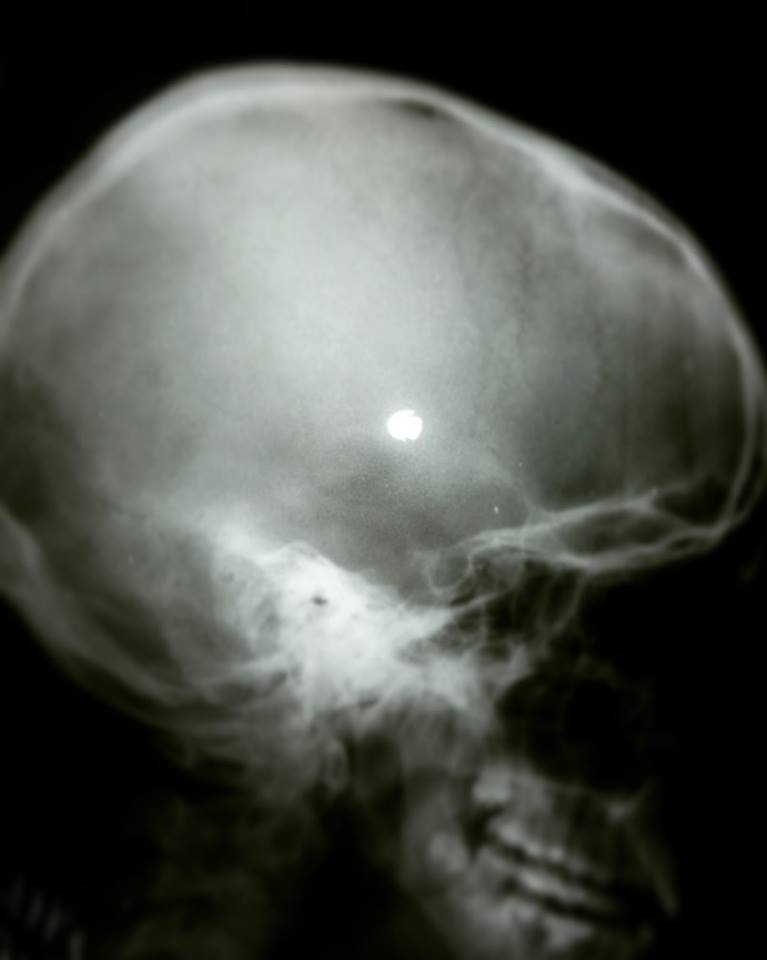

Нічні пригоди: лікарі дістали кулю з голови 16-річної дівчини

"Був такий випадок, пару місяців назад. Дівчинка 16 років, доставлена в травмпункт ВОДКЛ пізно вночі з кульовим пораненням голови. Куля увійшла над оком і "ковзнула" по черепу, зупинилася в м'яких тканинах скроневої області. В екстреному порядку викликали всіх фахівців, зробили КТ, приїхали нейрохірурги. Дитина вже виписана додому", - пише автор.Нагадуємо, Шестимісячний малюк помер після щеплення: мати звинувачує лікарів Читайте також: Забив до смерті під час безглуздої забави: трагічна смерть однорічної дівчинки